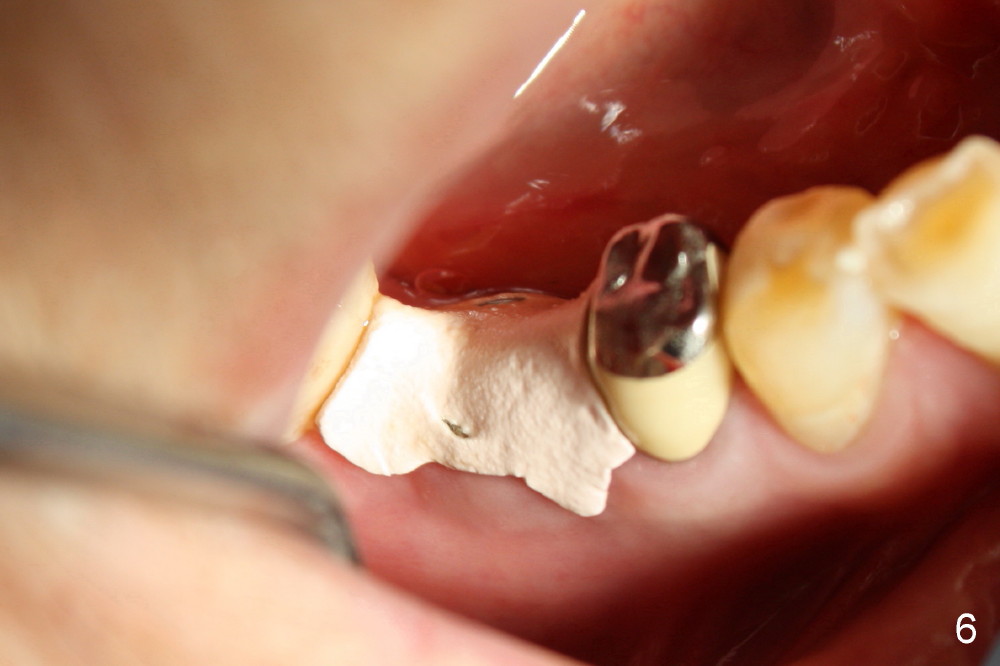

陈太太八十三岁,患Parkinson disease多年,行动不便,刷牙更不行。三年前请一位植牙高手为她右上六号牙植牙(图一mirror image),尽管服用抗菌素,术后七天植牙处出现红肿,炎性分泌物(图二箭头),大量生理盐水冲洗后,伤口表面好看些(图三箭头),最终感染得到控制。

几个月前右下六根尖周炎,根管治疗无效,Amoxicillin引起全身过敏性皮炎,最后拔除。术后六周伤口愈合,牙槽骨有些吸收(图四),通过骨扩张,植入6x17mm植牙(图五,牙槽骨好像不再萎缩了,与图四相比),伤口挺密合,不需要缝线,但是不是天衣无缝,细菌食物还是会进入伤口造成感染。服用抗生素好像不是个好主意(过敏史),灵机一动:使用periodontal dressing盖住植牙(图六)。但是术后病人抱怨局部肿痛,最后还是服用灭滴灵。术后第九天,患者回诊所左上七牙冠粘固,顺便拆除右下periodontal dressing(图六),dressing下面伤口愈合了吗?还是象图二那么糟(婚纱后面新娘漂亮吗)?